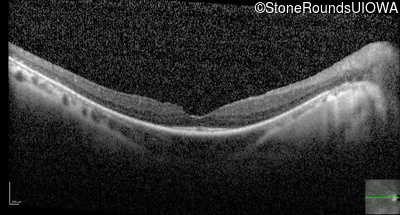

Optical Coherence Tomography - Left - 20/20 -2

Exemplar / OCT Stack